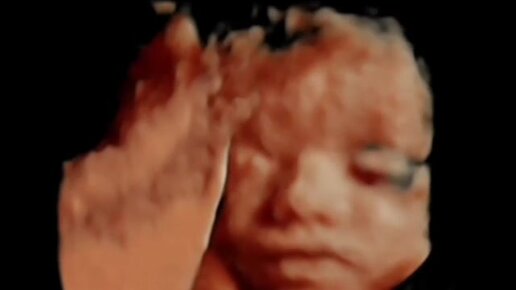

Что делает ребенок в утробе. 3D УЗИ